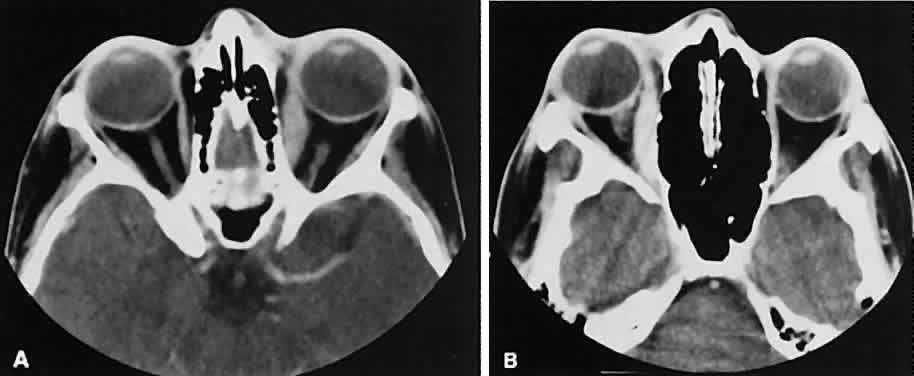

Nonspecific inflammatory dacryoadenitis shows enlargement of the lacrimal gland, which typically molds to the shape of the globe (Fig. 6). The adjacent bone is normal, and contrast enhancement of the gland usually is fairly homogeneous. Bilateral involvement may be apparent with certain conditions such as Sjogren's syndrome, sarcoidosis, lymphoma, or even Graves' orbitopathy, although enlarged EOM in the latter condition might make this a more obvious diagnosis.

Fig. 6. Nonspecific inflammatory dacryoadenitis. An isodense enlargement of the lacrimal gland is noted on axial (A) and coronal (B) views. Note the similarity to Figure 18.